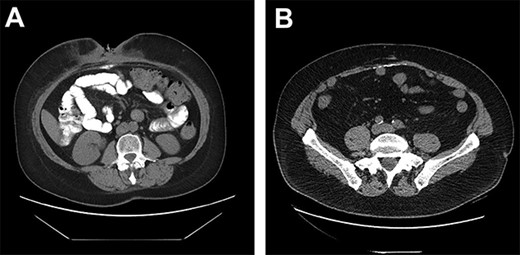

A 59-year-old female developed an incisional hernia following an open hiatal hernia repair. She underwent a repair with polypropylene mesh that was complicated by a mesh infection that required partial mesh explantation. Two years later, she re-presented with a recurrent midline incisional hernia. Her risk factors for infection included prior mesh infection, smoking and a body mass index (BMI) of 35. The hernia fascial defect measured by CT was 15 cm wide with a length of 10 cm. Pre-operatively, the patient quit smoking. One month prior to surgery, she underwent Botox injection of the abdominal muscles to facilitate fascial reapproximation. At surgery, bilateral anterior component separation with release of the external oblique muscles was performed, the fascia was closed primarily and the repair was reinforced with a 20 cm×30 cm porcine submucosa hernia graft (Biodesign® Cook Medical Ltd, Indiana, Unites States), placed intraperitoneally and anchored circumferentially with interrupted full thickness absorbable, monofilament sutures (#1 PDS® Medtronic Ltd., Dublin, Ireland). Stimulan 20 cc CSAB infused with vancomycin 4 gm and gentamicin 240 mg were utilized, with half of the beads placed on top of the mesh, below the fascia and the other half on top of the fascia in the subcutaneous space. We left a drain below the fascia on the mesh and one on each side deep to the subcutaneous flaps. We approximated the skin with a running 4–0 absorbable monofilament suture (Monocryl® Ethicon, Georgia, USA) and applied a Prevena™(KCI Technologies Ltd, San Antonio, Texas) negative pressure dressing over the incision. Operative time was 3 h 11 min. The patient had an uncomplicated early recovery and was discharged home on postoperative day 5. The patient returned 2 weeks later with a superficial wound dehiscence that was managed with negative pressure wound dressing. Five months later, the wound had still not completely granulated in and a CT scan demonstrated a (6×8 cm) abscess between the fascia and the mesh. The fascial closure remained intact and the abscess was managed by percutaneous drainage. Cultures demonstrated Candida albicans and the patient was treated with an 8-week course of fluconazole. During this time the percutaneous drainage ceased and the drain was removed. The patient presented to the emergency department 7 months later with worsening abdominal pain and a CT scan was performed (Fig. 1A). The report noted ‘an abnormal collection of oral contrast lying within the base of the anterior midline indicating there is a fistulous track communicating with an adjacent small bowel segment’. On the basis of the CT findings, she was advised by the on-call surgeon that she needed emergency surgery, mesh explantation and segmental small bowel resection. However, there was no clinical evidence of enteric discharge through the wound and the patient remained well with no fever and no elevation in white blood cell count. In consultation with the original surgeon, it was decided to forego emergency operative exploration and continue conservative management. Two months later, the subcutaneous wound had still not completely granulated and an exploration and debridement under general anesthesia was performed that failed to demonstrate an enteric fistula. The wound was eventually managed by local skin flap advancement.

(A) DC misinterpreted as extra luminal contrast consistent with a fistula. (B) DC distributed horizontally along the hernia graft in a patient where CSAB were used.

Only two cases of DC in incisional hernia repair have been previously described, both involving polypropylene mesh [6–8]. Both these cases described the calcium deposited in a vertical manner along the linea alba. Although it is rare for DC to be clinically relevant, it has been estimated that some degree of calcinosis occurs in up to 25% of laparotomies, usually as a punctate deposit in the midline, or along suture points of the anterior or posterior rectus sheath [9]. In our series of 23 patients undergoing incisional hernia repair with porcine submucosa hernia graft and CSAB, 6 of the 11 patients (55%) who had a post-operative CT had evidence of DC occurring horizontally along the hernia graft insertion plane (Fig. 1B).